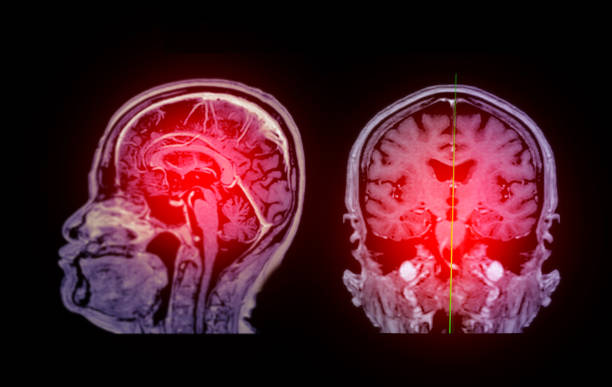

多項臨床前動物實驗表明,缺血性中風后干細胞移植可以顯著改善神經功能缺損。除了直接替代細胞外,干細胞還具有抗炎作用、神經保護作用、促進軸突再生、促進血管生成以及其他中風后過程(圖7)。